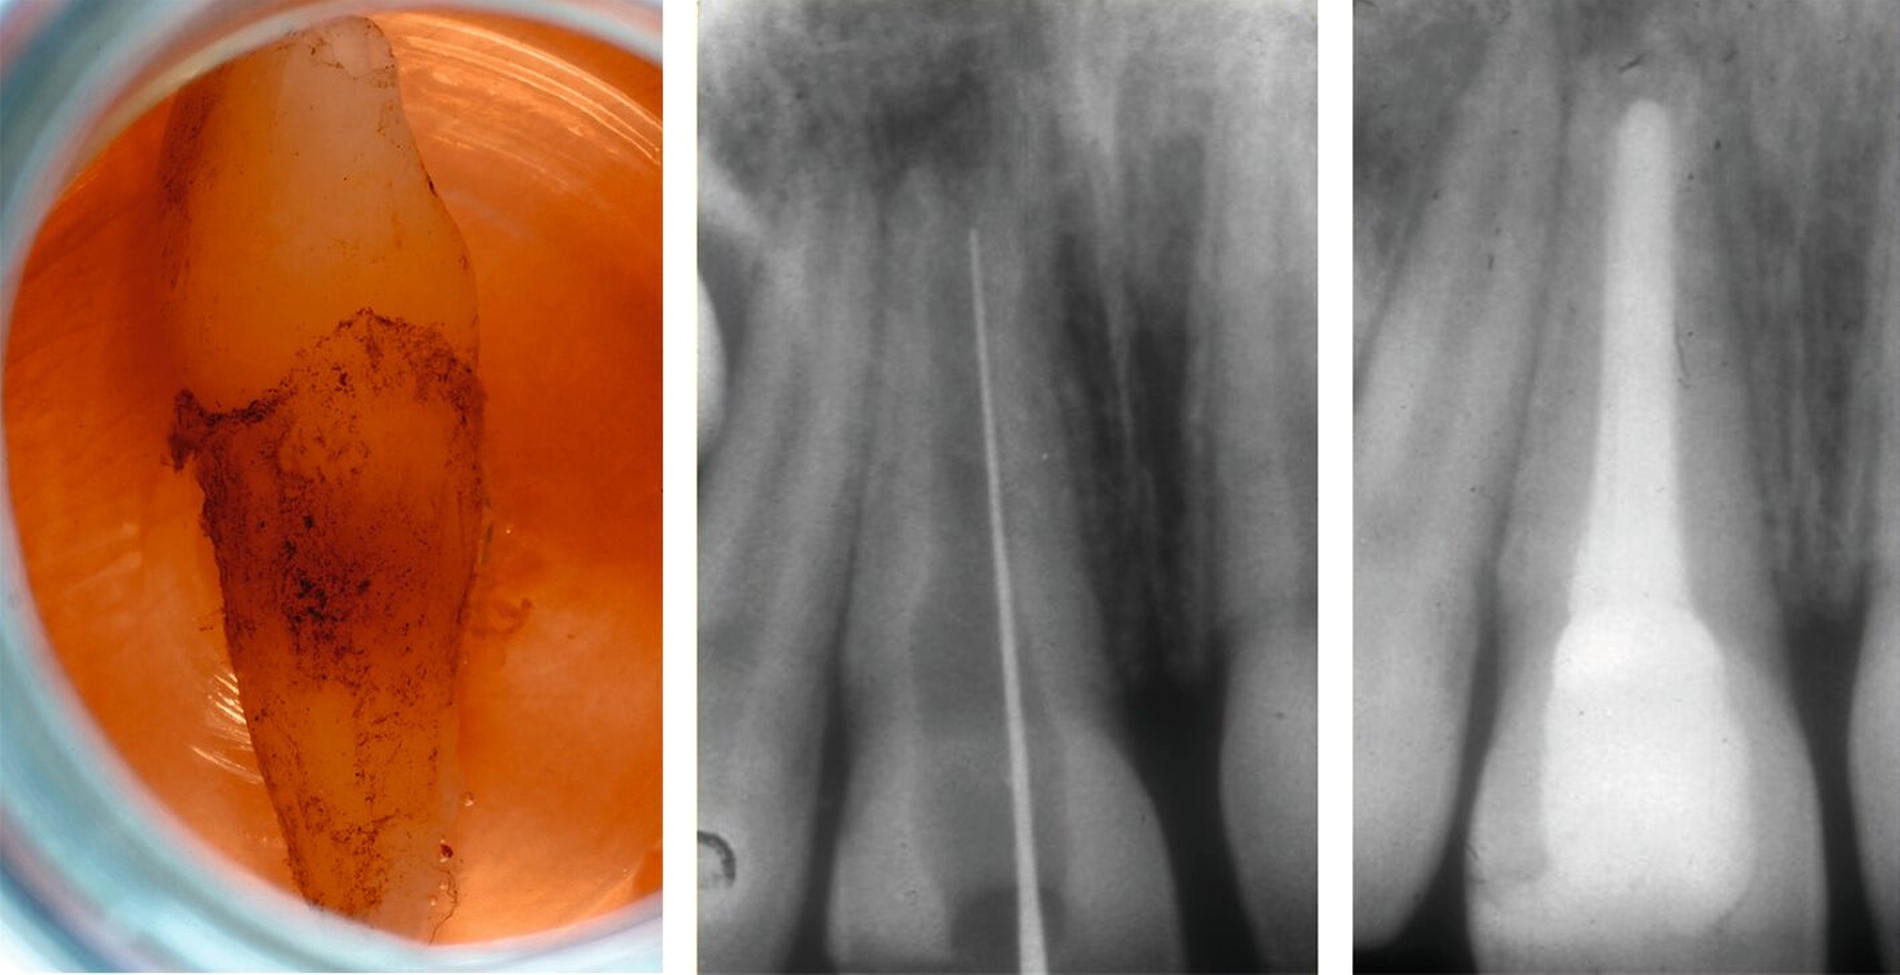

Dennoch kann es notwendig werden, auch bei Zähnen mit offenem Apex endodontische Maßnahmen einzuleiten. Ausschlaggebend ist dabei jedoch nicht die ausbleibende Reaktion auf den Sensibilitätstest, sondern die Entwicklung von Entzündungs- oder Resorptionsprozessen. Es sollte daher ein engmaschiger Recall durchgeführt und bei pathologischen Befunden eine Apexifikation eingeleitet, ein apikaler Verschluss mit hydraulischem Kalziumsilikatzement (Abbildung 5) oder eine Revitalisierung durchgeführt werden [Mente et al., 2013; Mente et al., 2009; Galler et al., 2016; Cvek, 1992].

Apikaler Verschluss durch Langzeiteinlage mit Kalziumhydroxid (Apexifikation): Bei Zähnen mit offenem Apex führen Langzeiteinlagen mit Kalziumhydroxid zur Induktion einer apikalen Hartgewebsbarriere, die günstigere Bedingungen für die Applikation einer konventionellen Wurzelkanalfüllung schafft. Hierzu sind raumfüllende Einlagen mit Kalziumhydroxid über mehrere Monate notwendig, wobei das Material in regelmäßigen Intervallen gewechselt wird (Abbildung 6).

Die Behandlung ist vergleichsweise einfach, kann über die gesetzliche Krankenkasse abgerechnet werden und weist eine hohe Erfolgswahrscheinlichkeit in Bezug auf eine periapikale Heilung auf. Problematisch ist allerdings die deutlich erhöhte Gefahr für zervikale Wurzelfrakturen, die abhängig vom Stadium der Wurzelentwicklung zwischen 28 Prozent und 77 Prozent liegt [Cvek, 1992]. Dies ist zum einen auf den negativen Einfluss der Langzeiteinlage auf die mechanischen Eigenschaften des Dentins zurückzuführen, zum anderen auf den Zeitraum von sechs bis 18 Monaten, in dem die dünnen Dentinwände im zervikalen Bereich nicht adhäsiv stabilisiert werden können (Abbildung 6).

Apikaler Verschluss mit hydraulischem Kalziumsilikatzement (apikaler Plug): Diese Therapie hat sich in den vergangenen zwei Jahrzehnten in vielen endodontischen Praxen zum Standardverfahren entwickelt. Hierbei wird nach adäquater Desinfektion des Wurzelkanalsystems ein biokompatibler hydraulischer Kalziumsilikatzement (zum Beispiel MTA) in einer Schichtstärke von circa 4 mm in direktem Kontakt mit den periapikalen Geweben eingebracht. Der restliche Wurzelkanal wird vorzugsweise mit Sealer und erwärmter Guttapercha gefüllt. Der anschließende Verschluss mit Komposit sollte tief genug eingebracht werden, um die zervikalen Kanalbereiche adhäsiv zu stabilisieren und einer Fraktur vorzubeugen (Abbildung 7). Die Erfolgsquoten für den apikalen Verschluss mit MTA liegen nach über vier bis acht Jahren bei über 90 Prozent [Mente et al., 2013; Re und Schwartz, 2017]. Der Nachteil des MTA-Plugs besteht in der erschwerten Entfernbarkeit im Fall einer notwendigen Revision. Die Behandlung ist im Vergleich zur Apexifikation mit Kalziumhydroxid aufwendiger und erfordert optische Vergrößerungshilfen für eine optimale Durchführung.